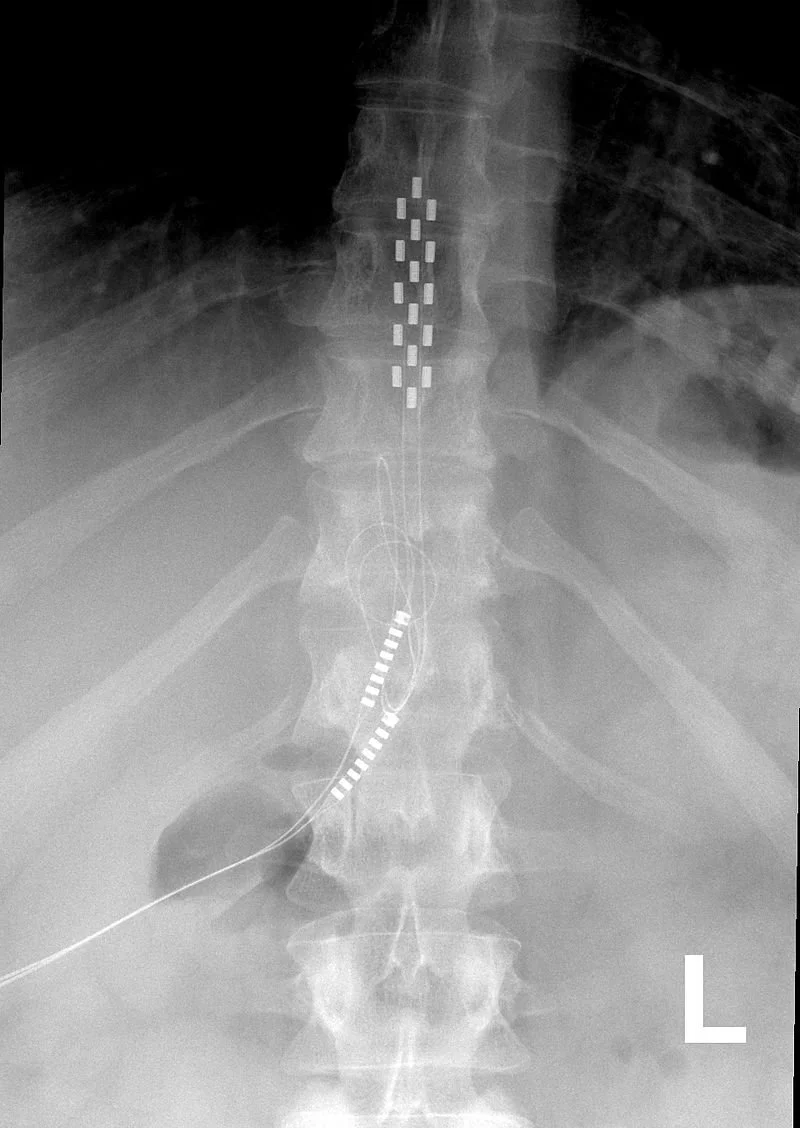

Pain treatments that will be reviewed under the WISeR Model include these procedures:

Electrical Nerve Stimulation

Deep Brain Stimulation for Essential Tremor and Parkinson's Disease

Vagus Nerve Stimulation

Surgical Removal or Ablation of Nerves

Epidural Steroid Injections (excluding facet joint injections)

Percutaneous Vertebral Augmentation (PVA) for Vertebral Compression Fractures

Cervical Fusions

Arthroscopic Surgery for Knee Osteoarthritis

Percutaneous Image-Guided Lumbar Decompression for Spinal Stenosis

Many of these treatments have already drawn scrutiny for being ineffective or costly. Studies have found that spinal cord stimulation, for example, has no benefit for back pain; while epidural steroid injections, nerve blocks and nerve ablation have been found to have little or no benefit.